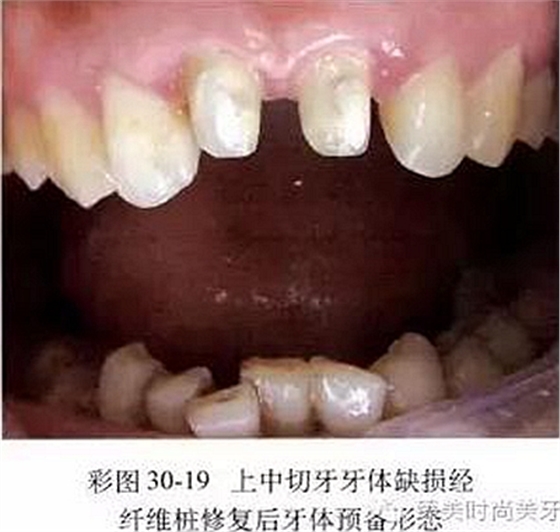

5.當(dāng)前牙牙體缺損大于1/3,并波及到牙髓時(shí),應(yīng)進(jìn)行完善的根管治療,然后采用成品纖維樁(如碳纖維樁、玻璃纖維樁、石英纖維樁)或二氧化鋯陶瓷樁放置在根管內(nèi)加強(qiáng)牙體組織的抗力,用與殘余牙體組織顏色相同的復(fù)合樹(shù)脂成核后按常規(guī)進(jìn)行牙體預(yù)備(彩圖30-19)。對(duì)于牙體缺損達(dá)到牙槽嵴頂時(shí),一般采用成品金屬樁樹(shù)脂核或鑄造陶瓷樁核進(jìn)行部分修復(fù),然后按常規(guī)進(jìn)行牙體預(yù)備。